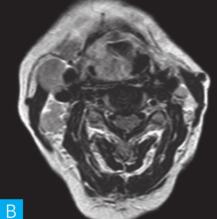

喉咽部MRI检查:病人采取仰卧位,横断位扫描为主,包括T1WI、T2WI及T2WI脂肪抑制序列,扫描范围自鼻咽部至喉咽以下,扫描层厚为3.5mm、层间隔0.35mm,矩阵512×512;辅以冠状位T2WI,矢状位T2WI序列及脂肪抑制序列,平扫后行横断位、冠状位及矢状位的增强扫描,造影剂量0.2ml/kg。见图1。

图1 咽喉部MRI:A.喉咽部MR横断面平扫T1WI;B.喉咽部MR横断面T2WI;C.喉咽部MR横断面T2压脂;D.喉咽部MR横断面增强T1WI;E.喉咽部MR冠状面T2WI;F.咽喉部MR冠状面增强T1WI

MRI平扫可见右侧扁桃体较大的软组织肿块,T1WI呈稍低信号,T2WI呈稍高信号,信号较均匀,T2WI压脂序列上呈高信号,病变与右侧咽扁桃体及舌根部分界不清,左侧咽扁桃体肿大,口咽腔明显变形狭窄,病灶延伸至喉前庭;双侧锁骨上窝及颈血管鞘周围间隙内可见多发大小不等的肿大淋巴结,大部分肿大淋巴结信号较均匀,呈稍高信号,边界清楚,右侧颈部间隙内个别肿大淋巴结内见少量斑片状液化坏死区;增强扫描后下咽部病变及双侧颈部间隙内的肿大淋巴结均呈明显的较均匀强化,提示该两处占位病变的血供较为丰富,且可能为同源性病变,因此采取“一元论”诊断思维进行分析更为合理。

(1)发现病变与认证:扁桃体及颈部病变较为容易发现,主要是分析两方面:一是仔细观察咽部有无原发病变,原发病变的形态及信号;二是评价淋巴结的分布,淋巴结的信号及生长特点。本病例基本征象为扁桃体病变信号均匀,无坏死,颈部淋巴结分布广泛,信号均匀。

(2)定位诊断:对于本病例来说,发现两处病变,包括咽部和颈部。咽部的病变位于扁桃体,延伸至喉咽腔,口咽腔和梨状窝受压变窄。颈部的病变为多发淋巴结增大,淋巴结广泛分布于Ⅱ~Ⅴ区。

本病例的特点为右侧扁桃体肿块,病变边界较清楚,表面光滑,信号均匀。双侧颈部间隙内多发肿大淋巴结,淋巴结围绕颈动脉鞘,部分病变融合倾向,广泛分布于Ⅱ~Ⅴ区,增强后病变较明显强化。

该病例首先对病变进行定位,包括咽部的和颈部的。咽部的病变:病变位于扁桃体,延伸至喉咽腔,口咽腔和梨状窝受压变窄(引起异物感和吞咽困难的原因)。颈部的病变:多发淋巴结增大,淋巴结广泛分布于Ⅱ~Ⅴ区。扁桃体病变的信号特征:扁桃体病变表面光滑,提示黏膜完整,病变来源于黏膜下,病变信号均匀,无坏死,进一步支持病变来源于黏膜下。颈部淋巴结病变的特征:淋巴结分布广泛,信号均匀(可以初步排除结核和转移,后两者容易坏死),围绕颈动脉鞘,但是不侵犯颈动脉鞘(转移容易侵犯颈动脉鞘),部分淋巴结融合倾向(结核淋巴结增大,无融合倾向,而且容易坏死),病变中度强化,进一步支持颈部淋巴瘤的诊断。诊断原则:首先仔细观察咽部有无原发病变,原发病变的形态及信号,尤其黏膜是否完整。其次评价淋巴结的分布,淋巴结的信号及生长特点。